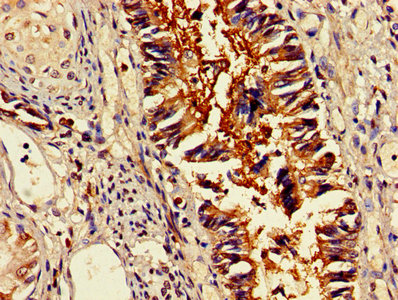

DescriptionOMA1 Polyclonal Antibody. Unconjugated. Raised in: Rabbit.

ImmunogenRecombinant Human Metalloendopeptidase OMA1, mitochondrial protein (22-194AA)

ApplicationELISA, WB, IHC, IF; Recommended dilution: WB:1:500-1:5000, IHC:1:200-1:500, IF:1:50-1:200